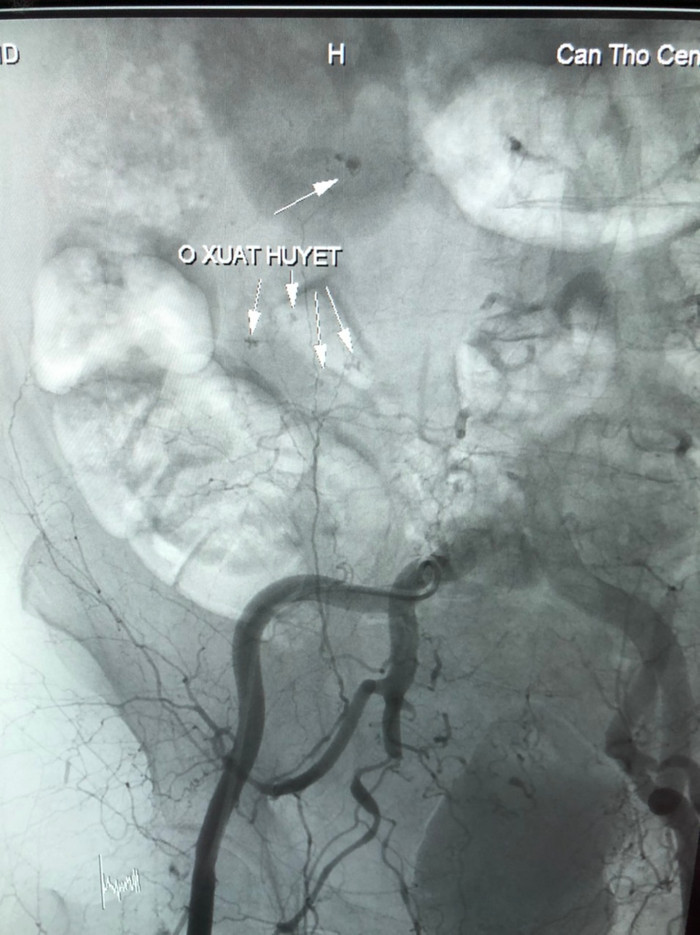

Các bác sĩ hội chẩn quyết định chụp và nút động mạch điều trị cầm máu các tạng số hóa xóa nền do BSCK1. Trần Công Khánh – Phó khoa Chẩn đoán hình ảnh thực hiện, kết quả ghi nhận đa ổ xuất huyết xuất phát từ nhánh động mạch thượng vị - dưới (P), tiến hành bơm hỗn hợp keo vào nhánh động mạch có thoát mạch.

Hình ảnh xuất huyết trước can thiệp.